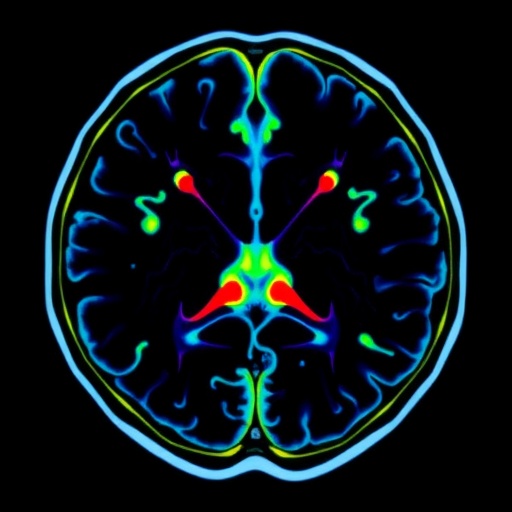

At the heart of MEDABIS-PRO lies an interdisciplinary endeavor integrating imaging science, radiation physics, biological assessment, and clinical translation. The focus is on Magnetic Resonance-integrated Proton Therapy (MRiPT), a state-of-the-art therapeutic approach that merges the unparalleled soft-tissue imaging capabilities of MRI and the highly targeted energy delivery of proton therapy. The project’s central scientific challenge revolves around the complex interactions between magnetic fields inherent to MRI systems and the dynamics of charged particles used in proton therapy. Specifically, the influence of magnetic field orientation and strength on charged particle trajectories—and thus dose deposition within tumor tissues—requires rigorous characterization and control to maintain treatment precision.

Magnetic Resonance Imaging has long been prized in oncological settings for its superior contrast resolution in soft tissues. Unlike conventional X-ray imaging methods, MRI avoids additional ionizing radiation exposure, making it an attractive candidate for real-time tumor tracking. The integration of MRI directly into proton therapy delivery facilitates adaptive approaches, enabling clinicians to accommodate patient and tumor movement during treatment. However, the introduction of a magnetic field fundamentally alters the charged proton beams’ paths via the Lorentz force, potentially modifying dose distributions in unintended ways. This interaction necessitates a comprehensive physical and biological understanding to ensure the therapeutic benefits of MRiPT outweigh any adverse dosimetric distortions.

Integrating magnetic resonance imaging into proton beam radiotherapy encapsulates a paradigm shift in oncological treatment. Proton therapy’s hallmark advantage—the precise dose localization defined by the Bragg peak—can be exploited more effectively when combined with MRI’s superior soft-tissue contrast and dynamic imaging. Real-time adaptation to anatomical changes during therapy sessions promises to reduce margins around tumors, potentially lowering toxicity while intensifying the dose to malignant tissue. The synergy of physics, biology, and engineering in MEDABIS-PRO illustrates the translational research needed to realize this vision.